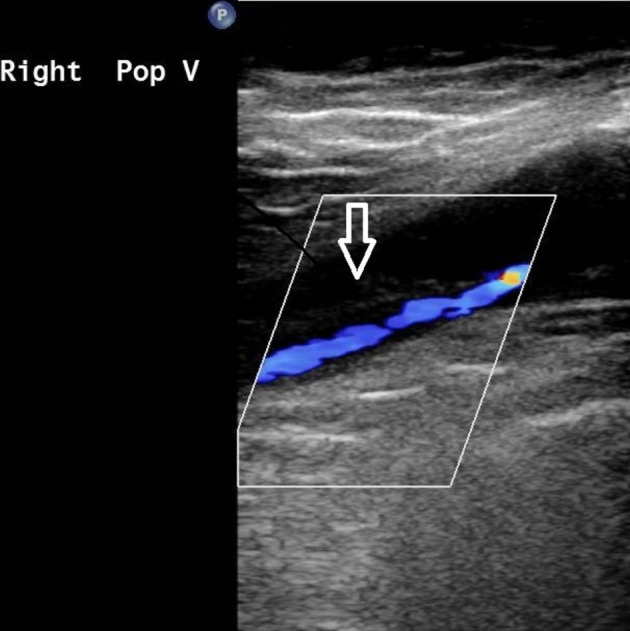

To further survey the pulmonary embolism, we conducted examinations in order to verify the possible etiology, including autoimmune disease markers (including antinuclear antibody, C3, C4, lupus anticoagulant, anticardiolipin immunoglobulin), tumor markers (including CEA, alpha-fetal protein, CA199, and PSA), coagulant function tests (including protein C function, antithrombin III, prothrombin time, partial thromboplastin time), all of which were within normal limits. Protein S function was 25.4% (normal value 62.6-150.4%) and the anti-platelet factor 4 (PF4) antibody titer was 50.01 ng/ml (cutoff value of 50 ng/ml) with an optical density of 0.424 units (weakly positive, cutoff value of 0.4 units). Left popliteal vein thrombosis was found by peripheral Doppler sonography (Figure 2).

Peripheral Doppler revealed probable thrombus with partial occlusion at the right popliteal vein (white open arrow).